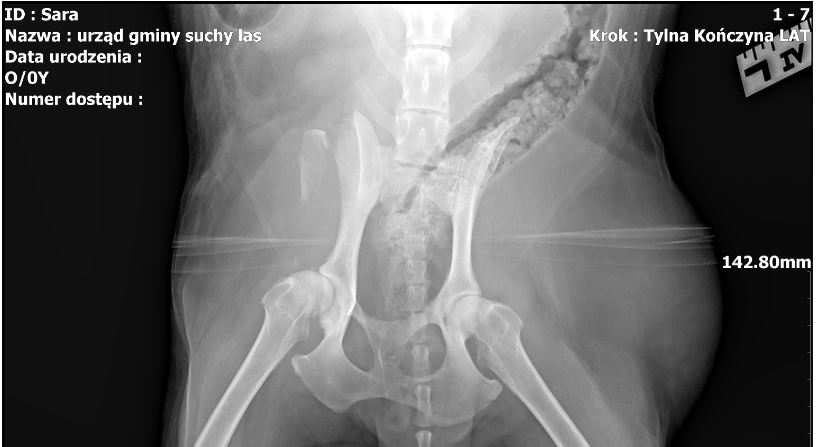

Zupełnie odmiennego zdania jest inny lekarz weterynarii, specjalista chirurg, którego poprosiliśmy o opinię na podstawie przesłanego zdjęcia RTG /wykonanego zresztą w klinice VET MED Sz. Szymczaka, dodajmy/; o tę opinię poprosiliśmy z powodu niemożności uzyskania jej od lek. wet. Szymona Szymczaka. W swojej opinii specjalista chirurgii weterynaryjnej, lek. wet. Mariusz Mikow, stwierdził, co następuje:

„Na dostarczonych obrazach rentgenowskich widoczne są:

1/ złamanie prawego guza biodrowego

2/ choroba zwyrodnieniowa obu stawów biodrowych średniego zaawansowania

3/ pozostałe uwidocznione odcinki miednicy i kończyn stosowne do wieku.

Zwyrodnienie stawów biodrowych może dawać objawy bólowe w sposób przewlekły, złamanie guza biodrowego daje ból ostry zwłaszcza przy próbach chodzenia.

Mariusz Mikow, Lekarz weterynarii, Specjalista chirurg /08554/”.

Dotarliśmy do nowego właściciela Sary, pana Krzysztofa, który zdecydował się na adopcję, mimo złego stanu zwierzęcia i poważnego urazu. Nowy właściciel potwierdza złamanie kości w wyniku potrącenia przez auto. Takie informacje, jak nam powiedział, przekazano mu w przychodni weterynaryjnej w Suchym Lesie VET-MED, gdy odbierał Sarę po zabiegach weterynaryjnych. Dysponuje też wypisem oraz dokumentacją weterynaryjną, z której niezbicie wynika, że pies doznał urazu kości, co widoczne jest też na zdjęciu RTG.

Na zdjęciu: Sara u nowego właściciela oraz prześwietlenie RTG Sary wykonane w gabinecie VET-MED w Suchym Lesie